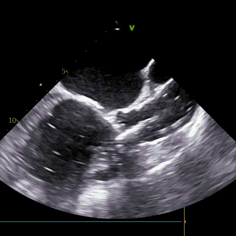

瓣周漏

术中导丝跨瓣后20mm球囊预扩,超声判断冠脉风险尚可,植入L23 VenusA Plus可回收瓣膜位置良好,用23mm球囊后扩支架下缘,微少量瓣周漏。